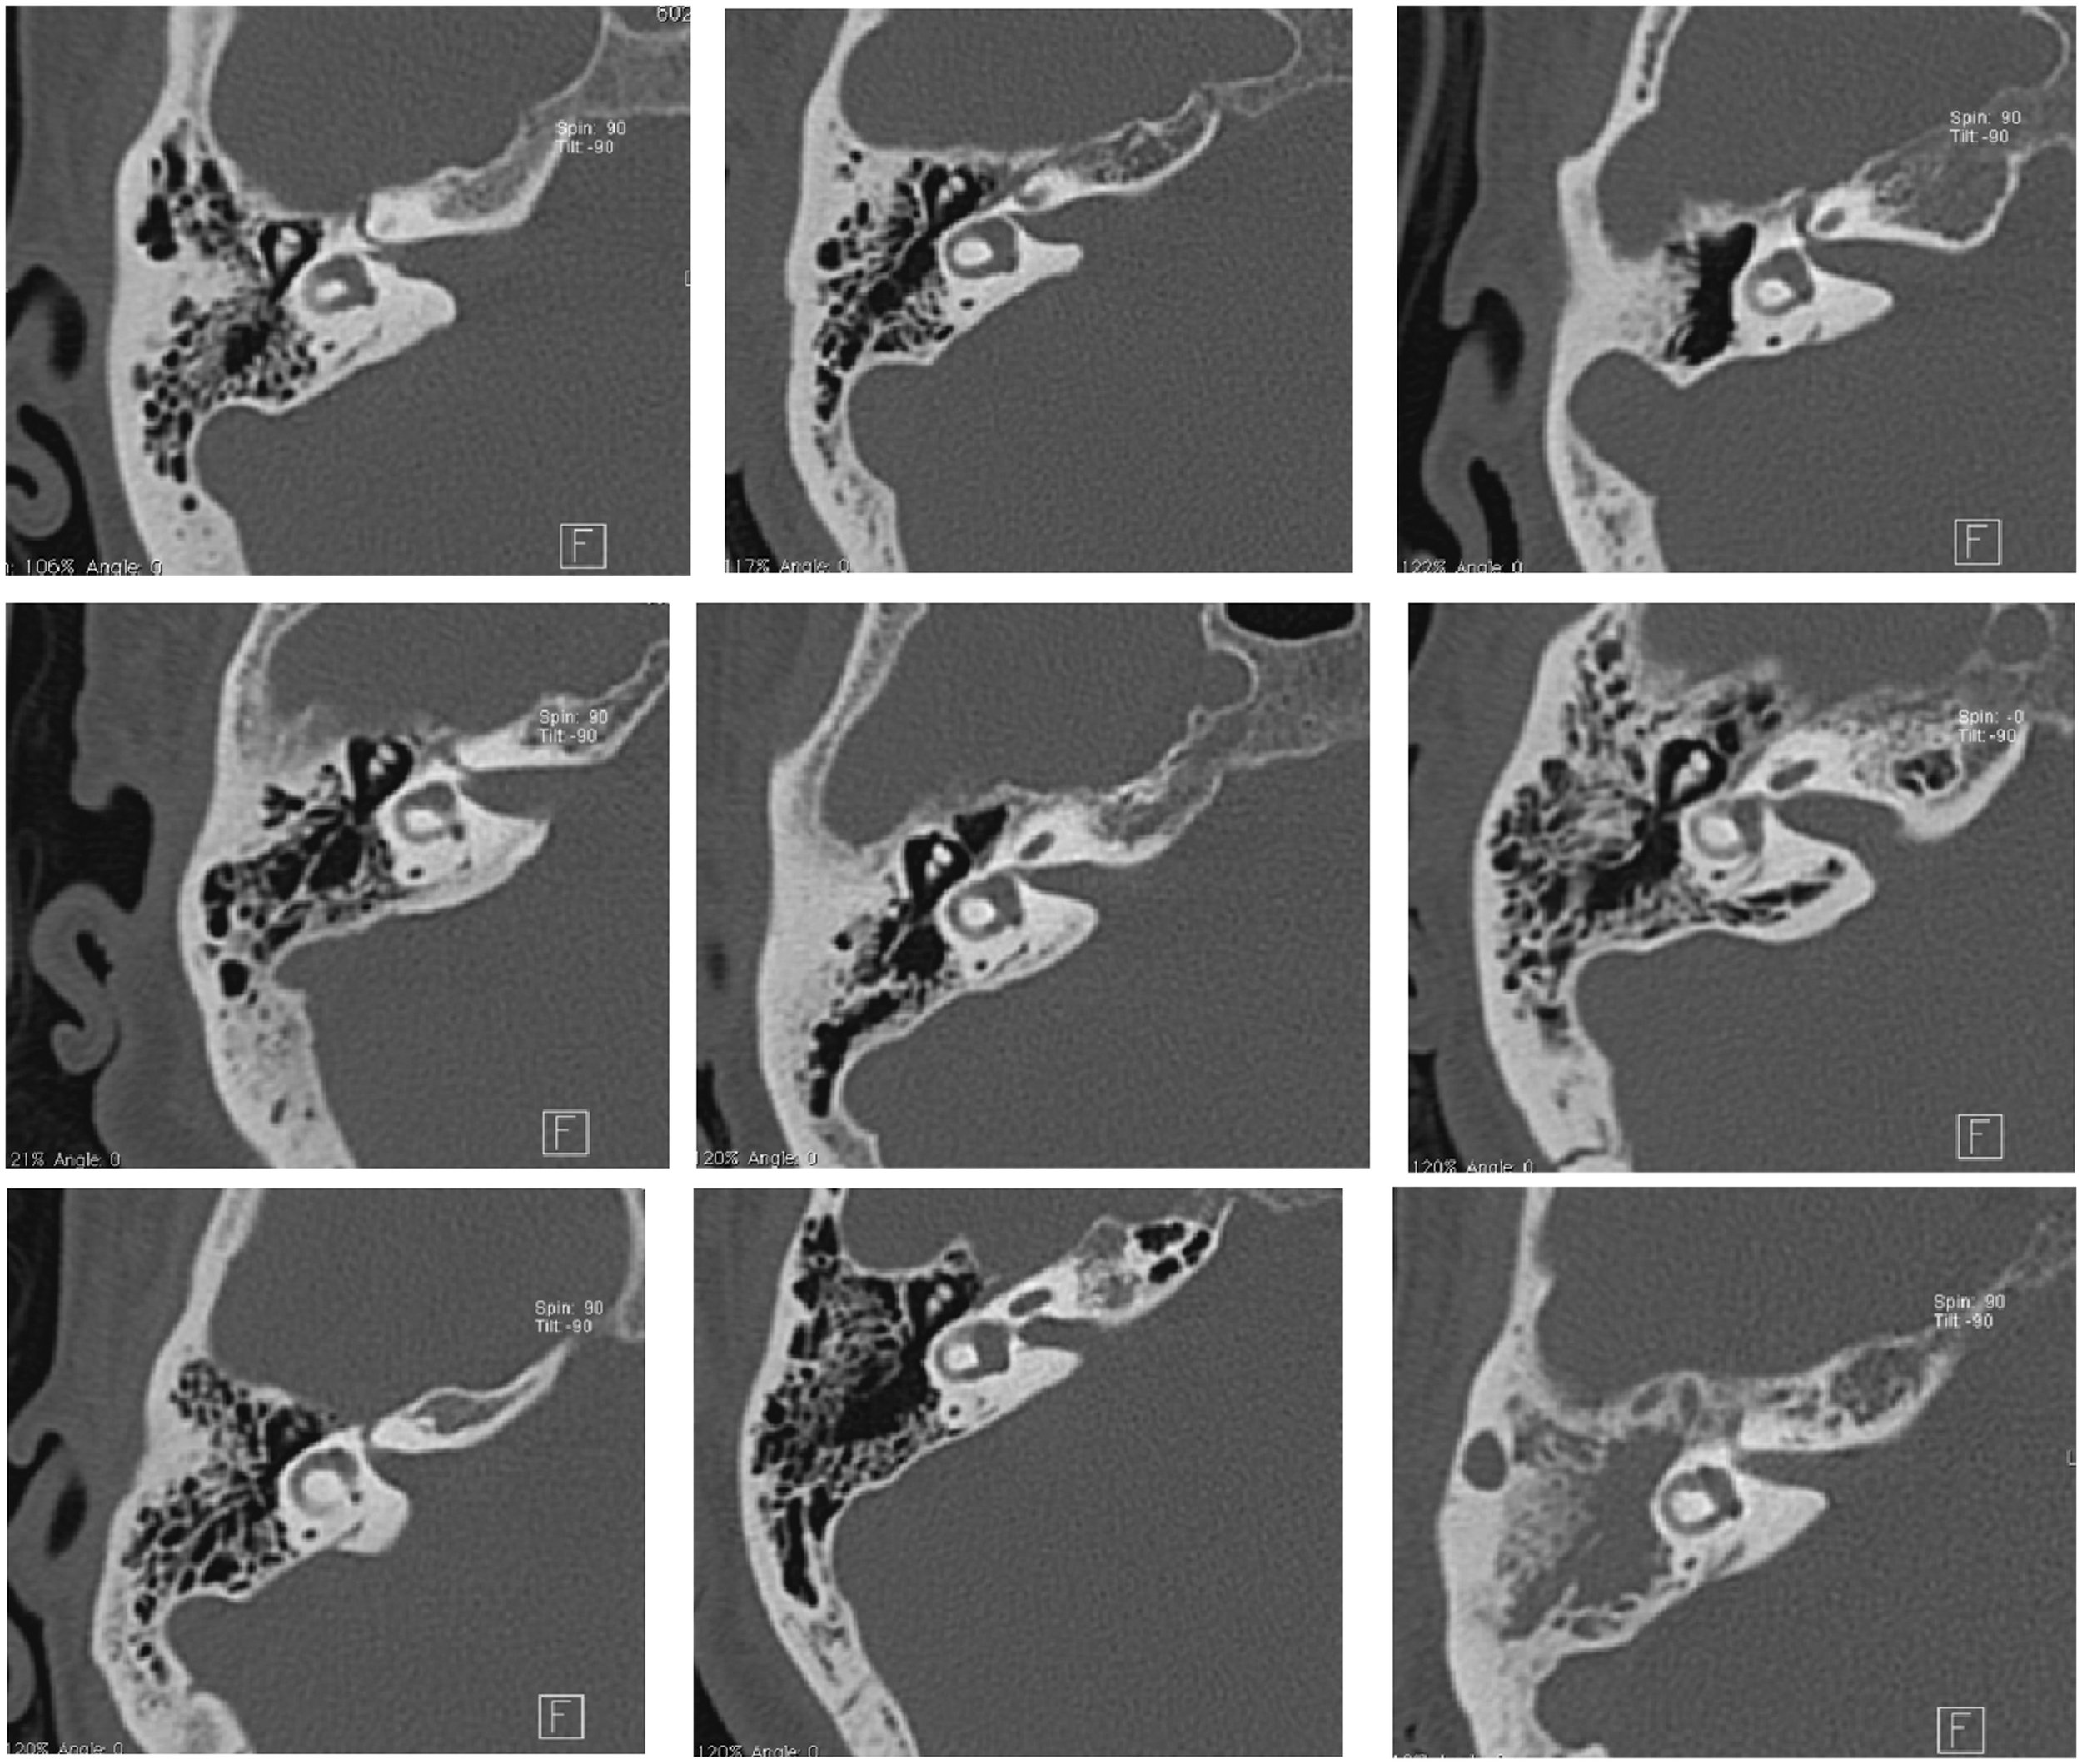

A collage of nine grayscale CT scan images of human ears from different angles.

High-resolution computerized tomography is an essential imaging modality to evaluate inner ear anatomy.

Before the cochlear implant surgery decision, a meticulous follow-up with hearing aids and detailed auditory tests are done. Also, imaging studies like computerized tomography, and magnetic resonance imaging are performed to evaluate developmental anomalies related to the inner ear and auditory nerve that may accompany hearing loss. Additionally, if necessary, meningococcal and pneumococcal vaccines are administered to cochlear implant candidates.